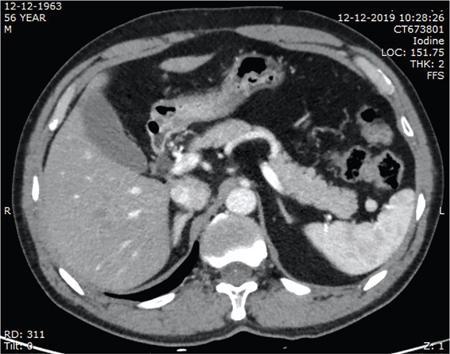

Vijay Kumar K.R. CONGENITAL SPLENIC ABNORMALITIES A multitude of variants and pathologies affect the spleen and it is pertinent for a radiologist to be aware of the common imaging appearances of the same. The spleen begins to develop in the fifth week of gestation from a mass of mesenchymal cells that condense between the two leaves of the dorsal mesogastrium. Several such aggregates fuse to form the lobulated embryonic spleen. The spleen is translocated to the upper left side of the abdominal cavity due to rotation of the stomach and differential growth of the dorsal mesogastrium. The mesogastrium fuses with the peritoneum over the left kidney and forms the splenorenal ligament. The lienorenal ligament fuses dorsally and the splenic artery courses behind the peritoneum as it enters the splenorenal ligament. The portion of dorsal mesentery between the stomach and spleen forms gastrosplenic ligament. Differentiated mesenchymal cells form the parenchyma, connective tissue and capsule of the spleen. The foetal spleen shows lobulations, which normally disappear before birth. However, they may persist along the medial part of the spleen. Sometimes a persisting portion of the spleen may extend medially and anteriorly over the upper pole of the left kidney. It may be mistaken for a space-occupying lesion arising from the kidney. Rarely it may extend posterior to the upper pole of the left kidney, displacing it anteriorly (Fig. 9.22.1.1). The notches and clefts along the superior borders are vestiges of the grooves that initially separated the foetal lobules. They may be 2–3 cm deep. They may mimic a splenic laceration in a patient with abdominal trauma, and the embedded peritoneum at the waist may simulate splenic infarction or haematoma. Hence caution should be exercised. A normal spleen which does not have a fixed ligamentous attachment can change position within the abdomen and is hence known as a wandering spleen. The spleen is normally anchored by the gastrosplenic and lienorenal ligament. Absence or weakness of one or more ligaments that affix the spleen. The spleen with its vascular pedicle as the sole attachment can become a hypermobile intraperitoneal organ. Rarely, the spleen may be normal in position with a wandering accessory spleen. Pregnancy (due to hormonal effects), prune belly syndrome, splenic cysts, malaria, Hodgkin’s disease and lymphangioma. Some of the affected patients may be asymptomatic and diagnosis may be incidental. Clinically it presents as a mobile, palpable, notched mass. Pressure on the vascular pedicle or torsion causes symptoms such as acute abdominal pain, nausea and vomiting. Torsion involving the tail of the pancreas may present as pancreatitis. Confirms the absence of spleen in the left upper quadrant of abdomen with identification of splenic tissue at an ectopic site. Power Doppler, colour Doppler and duplex sonography allow for the identification of blood flow in the splenic vessels and parenchyma. Intermittent torsion may be responsible for an enlarged spleen. Pathognomonic feature of wandering spleen is absence of the spleen in the upper abdominal cavity and presence of a well-demarcated, homogeneously enhancing mass of soft tissue in the pelvis or abdomen. Sometimes a wandering accessory spleen can be visualized as a long vascular pedicle connecting a small mass to the splenic vessels (‘jokari sign’). It can locate ectopic splenic tissue and can also indicate the viability of the tissue. Splenic vessel anatomy can be well demonstrated. 99mTc-sulphur colloid scintigraphy and heat denatured 99mTc-labelled red blood cell imaging provide useful information regarding size and location of splenic tissue. Torsion is indicated by lack of tracer activity in a previously demonstrated wandering spleen. Twisting and torsion of splenic artery can be demonstrated by celiac arteriography. The venous phase may demonstrate splenic vein obstruction with collateral circulation and varices. A congenital focus of normal splenic tissue that is separate from the main body of the spleen is known as an accessory spleen. It results from the failure of fusion of some embryonic splenic buds within the dorsal mesogastrium. Its incidence varies from 10% to 30% on autopsy examinations. They vary from a few millimetres to several centimetres in diameter. They most commonly are found around the splenic hilum. The second most common location is the pancreatic tail. They can also be found in the stomach wall, omentum, mesentery, large bowel and scrotum. Reveals a round or oval mass of tissue around the splenic hilum that is isoechoic with the main spleen. On noncontrast images they are isodense to the main spleen. CECT reveals serpiginous enhancement on arterial phase followed by homogeneous enhancement on venous phase-like spleen (Fig. 9.22.1.2). Accessory spleen is mildly hypointense to the spleen on T1 images and isointense on T2 images. Contrast administration reveals enhancement similar to that of spleen on the arterial, portal and late phases. It is isointense to spleen on DWI images with similar ADC values. 99mTc-sulphur colloid scintigraphy and heat denatured 99mTc-labelled red blood cell imaging show functional uptake in splenic tissue and differentiate splenule from other masses. PET CT-FDG avid mass can mimic tumour. Surgical resection is the preferred mode of treatment in the background of hypersplenism or lymphoma. It is characterized by an ectopic splenic tissue or an abnormal connection between the gonad and the spleen. The left side is more commonly involved than the right side. The accepted theory is that splenic gonadal fusion occurs due to abnormal attachment of the splenic anlage in the left dorsal mesogastrium with the left urogenital fold, during the fifth to eighth weeks of gestation. It has a higher male preponderance and can interfere with left testicular descent and closure of processus vaginalis. It commonly presents as inguinal hernia and cryptorchidism. The spleen and gonad are attached by a fibrous or splenic cord across the peritoneal cavity. It is associated with limb defect syndrome, cleft palate, micrognathia, anal anomalies, craniosynostosis, spina bifida, cardiac malformations, thoracic malformations and diaphragmatic hernias. This is not associated with congenital anomalies. Shows a well-defined scrotal mass with echotexture similar to that of spleen. Confirms splenic tissue in inguinal or scrotal area. It is characterized by the absence of spleen with duplication of right-sided structures. (Right isomerism). It has a slight male preponderance with an incidence of 1 in 40,000 live births. It has a poor prognosis due to its high association with congenital cardiac abnormalities (Fig. 9.22.1.3). It is of uncertain aetiology, and maybe associated with the mutations of CFC1 gene, SHROOM3 gene etc. Delayed development of embryonic curvature can be another cause. It is also theorized that it can be caused due to vascular compromise by pressure on splenic blood supply from adjacent structures. Splenectomy – Usually has a surgical history and is not accompanied by associated anomalies. It is a heterotaxy syndrome associated with multiple spleens and duplication of left-sided structures. (Left isomerism). It has an equal gender predilection with a slightly higher female preponderance. It has a fairly better prognosis than asplenia and is associated with a lesser incidence of cardiovascular anomalies (Fig. 9.22.1.4). It is of uncertain aetiology, and maybe associated with the mutations of CFC1 gene, SHROOM3 gene etc. Accelerated development of embryonic curvature can be another cause. SPLENIC INFECTION AND ABSCESS The infection of the spleen can show three patterns. Fungal and granulomatous infections usually present with multiple micronodules. A pyogenic abscess usually manifest as a solitary lesion. Imaging of diseases causing splenic nodules is never the sole basis for diagnosis. The clinical presentation and laboratory testing (tumour markers, tuberculosis testing and bone marrow biopsy) help in establishing an accurate diagnosis. The imaging findings are nonspecific and the nodules may vary in size from a few millimetres up to 2 cm in diameter. They maybe hypoechoic on ultrasound and hypoattenuating on CT. They are of low signal intensity on T1-weighted sequences and vary from hypointense to hyperintense on the T2-weighted sequences. The nodules show no enhancement or show ring enhancement after contrast study. Healed granulomas are seen as scattered, discrete, small calcifications in an otherwise normal spleen. With increasing number of immunocompromised patients, such as oncology patients undergoing aggressive chemotherapy, critically ill patients in intensive care units, injection drug abusers, and HIV-infected patients, there is rise in the incidence of splenic abscess. For splenic abscess to develop, it may require the presence of bacteremia (sepsis and septic emboli) and altered splenic architecture, which is caused secondary to a haematoma, infarct, or sickle cell disease. Abscesses can also develop from the extension of infection from adjacent organs, like in cases of infected pancreatitis and perinephric abscess, which are less common. In about 20% of cases, cause or source could not be discovered. Abscesses can be unilocular or multilocular, solitary or multiple, depending on the causative organisms and patient’s immunity. Mortality ranges from 15% in otherwise healthy patients with unilocular splenic abscess to 80% in immunocompromised patients with multiple abscesses. Abscesses which are multilocular, gas-containing or due to gram-negative bacillus show poor prognosis. A pyogenic abscess is usually solitary, unilocular/multilocular, but it can also be multifocal. These are uncommon and are reported in 0.14%–0.70% of large autopsy series. Most common presentation is fever (92%), left upper abdominal pain (77%) and leucocytosis (66%). Other symptoms are left pleural effusion and splenomegaly. It can be solitary or multiple, unilocular or multilocular. The appearance of splenic abscess depends on the stage of development. In the early stages of the disease, an abscess appears as an ill-defined mass later developing into a complex collection with septations, debris and sometimes gas. In later stages, after a capsule is developed, the lesion becomes well defined. Left pleural effusion is seen in around 42% of cases. Left lung base atelectasis in 20% of cases and splenomegaly is seen. Abscess with air can be identified based on the presence of extraluminal gas or air–fluid levels in the left upper quadrant. Ultrasonography has a sensitivity of 75%–98% in detecting splenic abscess. This is a very useful modality in patients who are bedridden, with renal impairment and for assessment of small splenic lesions (Fig. 9.22.2.1). Ill-defined hypoechoic mass mimicking a mass is seen in the early phase of the infection and a complex mass with internal septations, debris, rarely acoustic shadowing caused by gas is seen in later stages. The capsule appears as a thin hyperechoic rim. It is noninvasive, speedy, and a modality with high sensitivity (92%–98%). It helps in differentiating unilocular from multilocular lesions and, gives exact anatomical localization and information about perisplenic area, which later helps in planning-guided management procedures. An abscess is seen as a hypodense collection or complex cystic lesion with enhancing rim on the postcontrast study (Fig. 9.22.2.2). CT may help in identifying concurrent areas of infection and, thus, the source of infection. On CT, an abscess may look similar to an infarct, haematoma, or neoplasm. An infarct lacks mass effect, unlike abscess or tumour (Fig. 9.22.2.3). The presence of gas within the lesion is diagnostic of abscess; however, this finding is rare. Splenic abscesses show low signal on T1-weighted images and high signal on T2-weighted images compared with the normal spleen. Minimal to intense peripheral enhancement is seen after IV administration of gadolinium. But MRI is not routinely done, as many patients are clinically unstable. This plays a limited role in the detection and localization of splenic abscess. A nonspecific filling defect is seen on a 99mTc-sulphur colloid scan within spleen if the size is more than 2 cm in diameter. Normal inherent splenic activity on 67Ga scans and 111In-labelled leukocytes scans obscures any kind of inflammatory focus in the spleen, giving rise to false-negative examination. 67Ga scans are nonspecific as tracer uptake can be seen in neoplastic conditions such as lymphoma. Detection and characterization of the abscess are better done if 99mTc-sulphur colloid scan is done prior to 111In-labelled leukocytes scan. FDG PET/CT can also detect the site of infection but not used in the diagnosis of splenic abscess. Early diagnosis of an abscess is prompted for a better outcome. Based on laboratory findings, appropriate antibiotic therapy initiated. USG or CT-guided percutaneous aspiration is tried if the abscess is less than 5 cm in size, and for larger abscesses, percutaneous drainage procedures are done preserving the spleen. Splenectomy is reserved for complicated infections. Fungal abscesses are usually seen in immunocompromised patients with neutropenia such as patients with acquired immunodeficiency syndrome (AIDS), on chemotherapy and immune suppressive agents, and with lymphoproliferative disorders. With the advent of aggressive chemotherapy, the incidence of splenic fungal infections has increased. Approximately 7% of patients with acute leukaemia have hepatosplenic fungal infections. Multiple microabscesses are common. Hepatosplenic candidiasis lesions are very small, and before the advent of CT and MRI, their detection was too difficult. They measure in the range of 5–10 mm in diameter; however, they may be even miliary (<5 mm). Infections are mostly caused by candida species. Other organisms are aspergillus, Histoplasma and Cryptococcus. Imaging characteristics depend on the stage and severity of neutropenia. In cases of chronic disseminated infections with poor neutrophil counts, sometimes lesions are not visible as the host fails to produce an immune response. Lesions become apparent once neutrophil counts improve. Patients presenting with fever and splenomegaly are not improving on conventional antibiotic therapy, and with associated immunocompromised status, fungal infections are to be considered. No single imaging is specific or sensitive in establishing the diagnosis. Serial imaging is needed to detect hepatosplenic involvement; however, tissue diagnosis is the gold standard. Four different patterns are seen in hepatic candidiasis. Multiple, small, homogeneous hypoechoic nodules are the most common finding. Less commonly wheel-within-a-wheel appearance (i.e. the target sign) is seen in the early stage of infection. The first wheel is the peripheral hypoechoic zone of fibrosis and an echogenic second wheel of inflammatory cells around a central hypoechoic nidus containing necrosis and fungal elements. Later these lesions evolve into Bull’s eye lesion where there is a central echogenic focus surrounded by a hypoechoic halo. Lesions become small and hyperechoic with various degrees of posterior acoustic shadowing, with or without calcification, or they may even disappear later in the course of the infection. Splenic nodules are hypodense lesions measuring in the range of 5–10 mm. Only 30% of cases are detected in noncontrast studies. They often have low attenuation, although there can be a focus of high attenuation or a ‘wheel-within-a-wheel’ pattern. Peripheral ring of enhancement is noted in around 70% of cases in the arterial phase of CT, and it is said to disappear on the portal venous phase. There is no significant difference in the detection of the lesions between arterial and portal venous phases of contrast studies. MRI is said to be the investigation of choice for diagnosis of hepatosplenic candidiasis and is superior to CT and USG, especially when short-time inversion recovery sequence is used. MR imaging is also used to monitor the response to antifungal therapy. Based on MRI findings different phases of hepatosplenic candidiasis are described. Lesions are small, measuring less than 1 cm in diameter. They show mildly hypointense on the T1-weighted images and markedly hyperintense on the T2-weighted images. In 2 weeks to 3 months, acute lesions are transformed into subacute lesions. The lesions reveal mildly increased signal on both T1- and T2-weighted sequences. On all sequences, a peripheral ring of very low signal intensity is seen. Following the gadolinium administration, the central region of the lesions show enhancement; however, the peripheral ring continues to have low signal intensity, making them more obvious. It takes from 3 months to more than 1 year for the healed fungal foci composed of fibrous tissue of differing densities and degrees of vascularization to appear on MRI. The lesions measure 1–3 cm, become irregular, and the central area disappears. Chronic healed fungal abscesses have low signal intensity on T1-weighted images and are isointense to mildly hyperintense on T2-weighted images. No perilesional dark ring is noted. These lesions are moderately hypointense on early postgadolinium images and minimally hypointense on delayed postgadolinium images. Mycobacterial tuberculosis infections are mainly seen in immunocompromised patients. Spleen involvement is seen in disseminated, miliary infection in about 80%–100% of autopsy cases; however, it is documented less on imaging. Splenic tuberculosis is seen in the form of nodules measuring ∼ 0.2 and 1 cm in diameter. The macronodular form is very rare (Fig. 9.22.2.4). Hypoechoic pattern is seen. Hypoattenuating nodules with lymphadenopathy noted. Depending on the different stages of the tubercular process, intensities on T1- and T2-weighted images vary. On contrast-enhanced T1-weighted images, lesions most often show peripheral enhancement less commonly gradual peripheral enhancement with complete filling is noted. It is also called as Mycobacterium intracellulare infections. These are also typically seen in immunocompromised patients. Splenomegaly with multiple, low attenuation nodules is seen. Associated findings such as hepatosplenomegaly, diffuse jejunal wall thickening and enlarged lymph nodes are seen. Lymph nodal involvement is homogeneous as opposed to Mycobacterium tuberculosis infections. Focal splenic or hepatic lesions are noted in about 30% of patients with HIV who are infected with M. tuberculosis but are rarely noted in those infected with M. avium intracellulare. Marked splenomegaly is more common in M. avium intracellulare than in M. tuberculosis infection. It is a common opportunistic infection in patients with HIV. Extra pulmonary involvement manifested in the form of necrotizing granulomas. Spleen involvement is an incidental finding. When treated the nodules may enlarge and become progressively calcified in a rim like or punctate fashion. Disseminated infection can show punctate calcification in adrenal glands, pleural or peritoneal effusions, that subsequently calcify. Splenomegaly with small hypoechoic lesions with cystic components or tiny, highly reflective, nonshadowing foci or calcified granulomas. The nodules are hypodense. Calcified granulomas are seen in later stages. This is a self-limited disease caused by bartonellae henselae. Hepatosplenic involvement is rare. This disease is to be considered when a patient presents with abdominal pain, fever of unknown origin, and multiple hypodense lesions in the liver and spleen. It is also called as echinococcosis, a disease seen in endemic regions and in patients emigrated from endemic areas. The causative organism is a zoonotic tapeworm echinococcus granulosus. The most commonly involved organs are the liver, lung, peritoneum, kidney, brain, mediastinum and heart. Spleen is rarely primarily involved. Spleen is involved in approximately 2% of cases of abdominal hydatidosis. Spleen involvement is seen in case of an extensive abdominal hydatidosis, like after the rupture of liver hydatid cyst or in cases of systemic dissemination of infection. Larvae of the tapeworm incite an inflammatory response after its entry into the target tissue in the host where it forms a hydatid cysts consisting of three layers. Peri cyst is an outer layer of modified host cells forming a dense and fibrous layer. The middle layer laminated layer and an inner germinal layer made up of daughter cysts, also called as brood capsules. Scolices develop in the brood capsules. The laminated and germinal layer forms the true cyst wall. After the parasites die, the cysts become inactive, may calcify, and undergo fibrosis. Patients present with abdominal pain, splenomegaly and fever. The diagnosis is to be suspected in all patients from endemic areas presenting with a splenic cyst. A World Health Organization Working Group on echinococcosis has a standardized sonographic classification of echinococcal cysts (Table 9.22.2.1). CE, cysticechinococcosis; CL, undifferentiated simple cystic lesions. Radiological appearances depend on the natural aging process of the cyst. Classic imaging characteristics are lost when the cyst becomes secondarily infected. A ring-like or curvilinear calcification noted in the left hypochondriac region. This may represent the calcification of pericyst in later stages of the disease. Ultrasound is an easy and most commonly used for evaluation of a suspected case of abdominal echinococcal disease. It is used for the diagnosis, planning the management and follow-up. Shifting of brood capsules within the cyst causes fine internal echoes, that is ‘The snowflake sign’ (hydatid sand). Detached laminated endocysts may be seen within the cysts, that is ‘The. Waterlily sign’. Mother cysts may be partially /completely filled by daughter cysts. Calcifications with posterior acoustic shadowing are seen in later stages of the disease. CT and MRI are indicated for widespread disease and complications and for planning percutaneous therapy and surgery. Complications of a hydatid cyst include compression of the adjacent structures, cyst rupture, secondary infections, anaphylaxis and fistulization to surrounding structures. A hydatid cyst may be seen as a well-defined, hypoattenuating cystic lesion with fluid-attenuation values and a distinguishable wall. CT is more sensitive for subtle wall calcification. May appear hyperdense because of debris, hydatid sand and inflammatory cells (Fig. 9.22.2.5). In CE 2 cysts, peripherally arranged daughter cysts, completely fill them other cyst. The daughter cysts show lower attenuation than the mother cyst. Type CE 3 lesions are round or oval with occasional calcification and daughter cysts. They usually show high attenuation. Type CE 4 cysts are complex masses. Intravenous contrast administration reveals enhancement of septa and cyst wall. Type CE 5 cysts are complex cystic or solid-looking lesions, and they can be partially or completely calcified. The simple cysts show low signal on the T1-weighted images and markedly hyperintense on the T2-weighted images. The rim sign which is a low signal intensity rim well seen in T2-weighted MRI images is characteristic of hydatid disease. Enhancement of septa and cyst wall is noted after the intravenous administration of gadolinium. On T1- and T2-weighted images, the maternal matrix appears hyperintense relative to the daughter cysts. The collapsed parasitic membranes may show serpent sign or snake sign, which are hypointense on all sequences. Hypointensity on T1- and T2-weighted images are seen in type CE 4 and CE 5 cysts. The imaging findings combined with the clinical, immunologic testing and epidemiologic results, usually provide the correct diagnosis. Seen in cases of tuberculosis, histoplasmosis, less commonly in Pneumocystis jirovecii pneumonia and brucellosis. These are incidental findings usually preceded by hypoattenuating microabscesses. Microabscesses heal with or without preceding regression. More than five calcifications usually represent histoplasmosis, whereas less than five represent tuberculosis. A ring-like calcification is seen in Pneumocystis carinii pneumonia. Any granulomatous infection is more likely to involve other organs such as the liver, kidneys and lymph nodes. Hydatid cysts can show ring-like or curvilinear calcification (Fig. 9.22.2.6). SPLENOMEGALY AND HYPERSPLENISM Splenomegaly is often a nonspecific finding, and there are many causes for splenomegaly. The spleen can grow into large sizes towards right iliac fossa, crossing midline. On average adult spleen measures <11 cm in length,<7 cm wide,<5 cm thick, and weighs approximately 150 g (80–300 g). The size and weight of the spleen decrease with advancing age. Spleen size is significantly influenced by the sex and body height of an individual. Chow et al. assessed 1230 healthy volunteers and found that spleen length and volume were significantly and independently associated with sex, body height and weight. Taller and heavier male individuals have larger and longer spleens. In one study the spleen length in 6% of women, and 26% of men exceeded a strict upper limit of normal of 12 cm. Rosenberg et al. established an upper limit of standard splenic length of 12 cm for girls and 13 cm for boys (≥15 years). Massive splenomegaly is defined as a spleen size greater than 18 cm, is less common and includes haematological disorders and infections (Table 9.22.3.1).